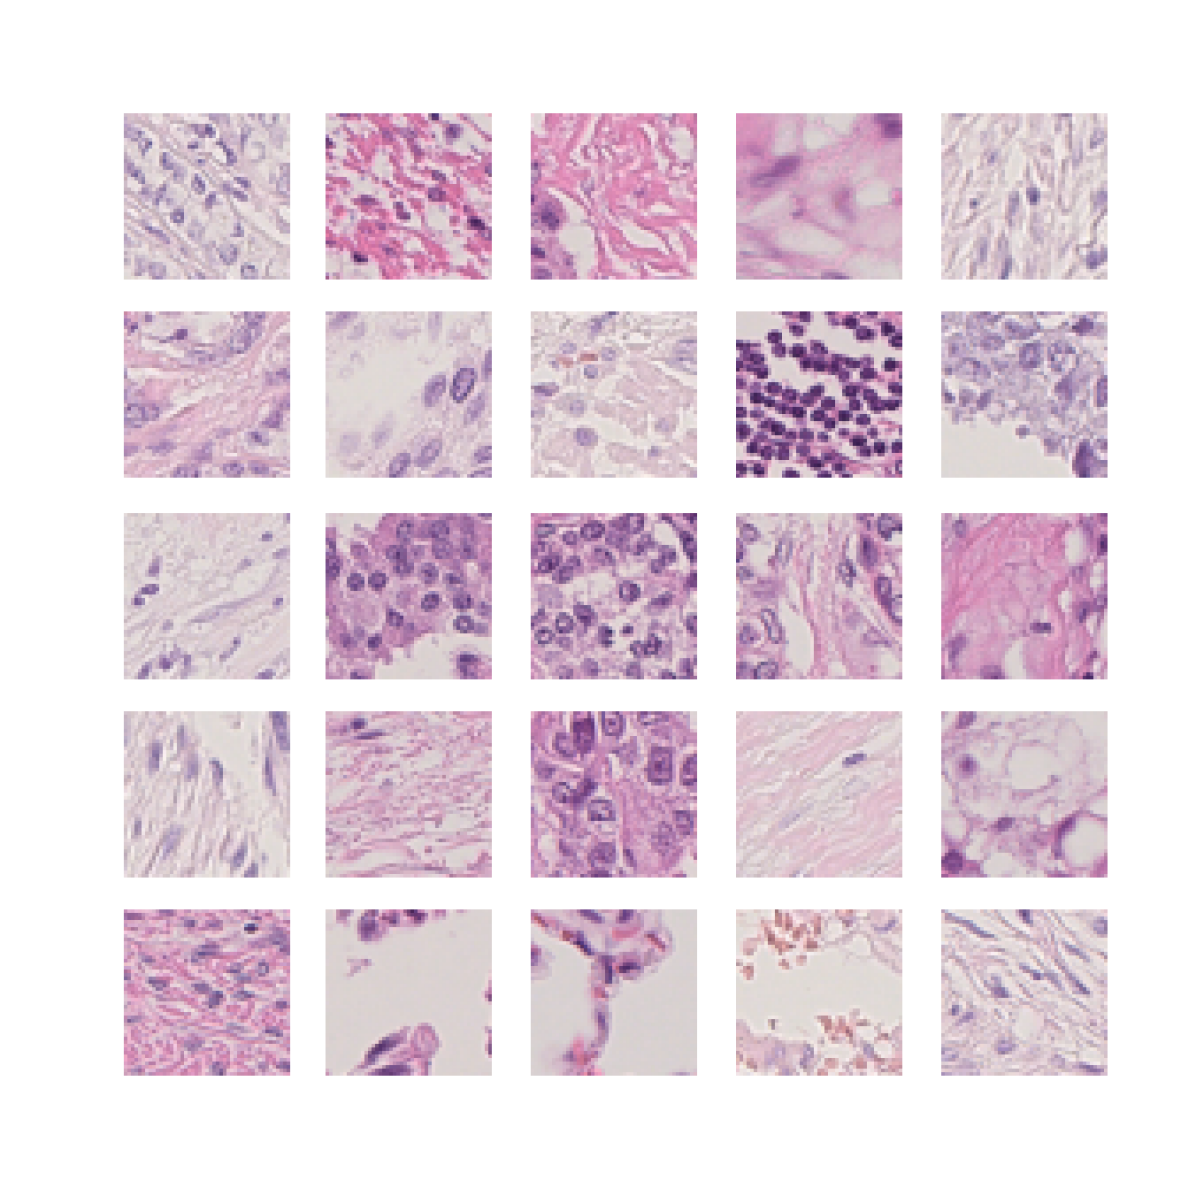

We also analyse the activation maps for each model using GradCAM as described in section S3. This offers more insight into the areas of the image which are contributing most heavily to the models’ representations. In Figure 4(b) we present some representative examples, however, a larger selection which was chosen at random is presented in Figures S10 to S25. The larger selection makes it easier to see the emergent patterns, including that privileged Siamese models tend to mainly identify features which are strongly present in both inputs, while unprivileged Siamese models tend to learn more diffuse features that are not specific to one cell phenotype or image region. TriDeNT ♆ incorporates both sets of features, learning both features specific to the privileged data and more the general features associated with unprivileged Siamese networks.

We can see in Figure 4(b) panel A that for ERG, the privileged Siamese model focuses almost exclusively on any nuclei which could be endothelial cells. As there are very few endothelial cells in the dataset, it could be an effective strategy to identify anything that could potentially be an endothelial cell to minimise the difference between the representations of the H&E model and the IF mask model. In the corresponding unprivileged Siamese image, we see that the model identifies some of these nuclei, albeit less strongly, but also focuses heavily on the other tissue and even the background, while strongly fixating on two spots of debris in the center of the image. This model has less ‘incentive’ to learn the weak features related to endothelial cells as these occur rarely and are not easy to detect, while more generic strong features such as the presence of connective tissue and the prevalence of background are more common and predictable from augmented images. We see that TriDeNT ♆ combines these two feature sets, strongly identifying nuclei while also identifying the connective tissue.

In panel C we see a similar pattern, with the privileged Siamese model fixating solely on the nuclei, while the TriDeNT ♆ model takes a more balanced approach. The unprivileged Siamese model appears to focus on a single cluster of nuclei while neglecting others, and similarly identifies an area of fibroblasts with its distinctive pattern but does not others.

In contrast to panels A and C which represent models with poor privileged Siamese results, panels B and D represent models whose privileged Siamese results were comparable to both TriDeNT ♆ and even the supervised baseline. It is therefore interesting to note that there are far more similarities between the privileged Siamese and TriDeNT ♆ models in both cases. Particularly in panel B, TriDeNT ♆ and the privileged Siamese model return virtually identical heatmaps, with both strongly identifying epithelial nuclei and neglecting the same areas of connective tissue. The unprivileged model in this case appears to focus solely on the centre of the image, giving a significantly different heatmap to the other panels.

Panel D again shows the previous pattern, with the privileged Siamese model identifying the features strongly present in the privileged data – fibroblasts – while neglecting the nuclei present. TriDeNT ♆ also strongly identifies the connective tissue, but, unlike the privileged Siamese model, does not completely neglect the nuclei. The unprivileged Siamese model primarily identifies background, and does not appear to identify the nuclei in this example.